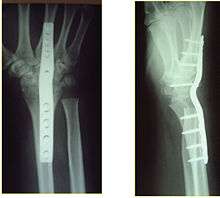

Surgery

Contemporary surgical options have improved treatment of this injury. Techniques include Open Reduction Internal Fixation (ORIF), external fixation, percutaneous pinning, or some combination of the above. Significant advances have been made in operative open reduction and internal fixation. Two newer treatment are fragment specific fixation and fixed angle volar plating. These attempt fixation rigid enough to allow almost immediate mobility, in an effort to minimize stiffness and improve ultimate function, although there has been no demonstration of improved final outcome from early mobilization (prior to 6 weeks after surgical fixation). Although restoration of radiocarpal alignment is thought to be of obvious importance the exact amount of angulation, shortening, intra articular gap/step which impact final function are not exactly known. The alignment of the distal radioulnar joint is also important as this can be a source of a pain and loss of rotation after final healing and maximum recovery.

Prognosis varies depending on dozens of variables. If the anatomy (bony alignment) is not properly restored, function may remain poor even after healing. Restoration of bony alignment is not a guarantee of success, as there are significant soft tissue contributions to the healing process.